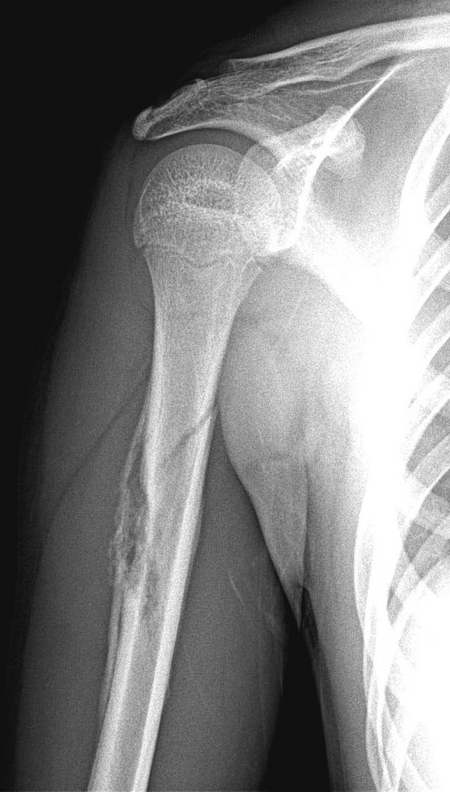

标题: X0799:右肱骨恶性骨肿瘤?,讨论!

原无外伤史,男,16y,右上臂轻微外伤 前来就诊。

骨膜反应.伴病理性骨折...考虑骨肉瘤

尤文氏瘤合并病理性骨折;16岁,骨髓腔有破坏.但不能除外感染可能

肱骨骨干皮质及髓腔骨质破坏伴层状骨膜反应与线形骨折,结合病史考虑骨恶性肿瘤伴病理骨折,类型难以定论[骨肉瘤-------一般发生于干骺端],[尤文氏瘤发生骨干]

骨膜反应非常广泛,且有中断征象,皮质破坏,髓腔也有破坏,病人16岁,首先认为恶性肿瘤,(骨肉瘤吧)

骨膜反应广泛,皮髓质溶骨性破坏,病理性骨折,恶性肿瘤可能性大。

肱骨隋腔密度不均匀减低,邻近皮质破坏,有明显骨膜反应,骨折为病理性的,考虑年龄仅16岁,尤文氏瘤伴病理骨折可能性大